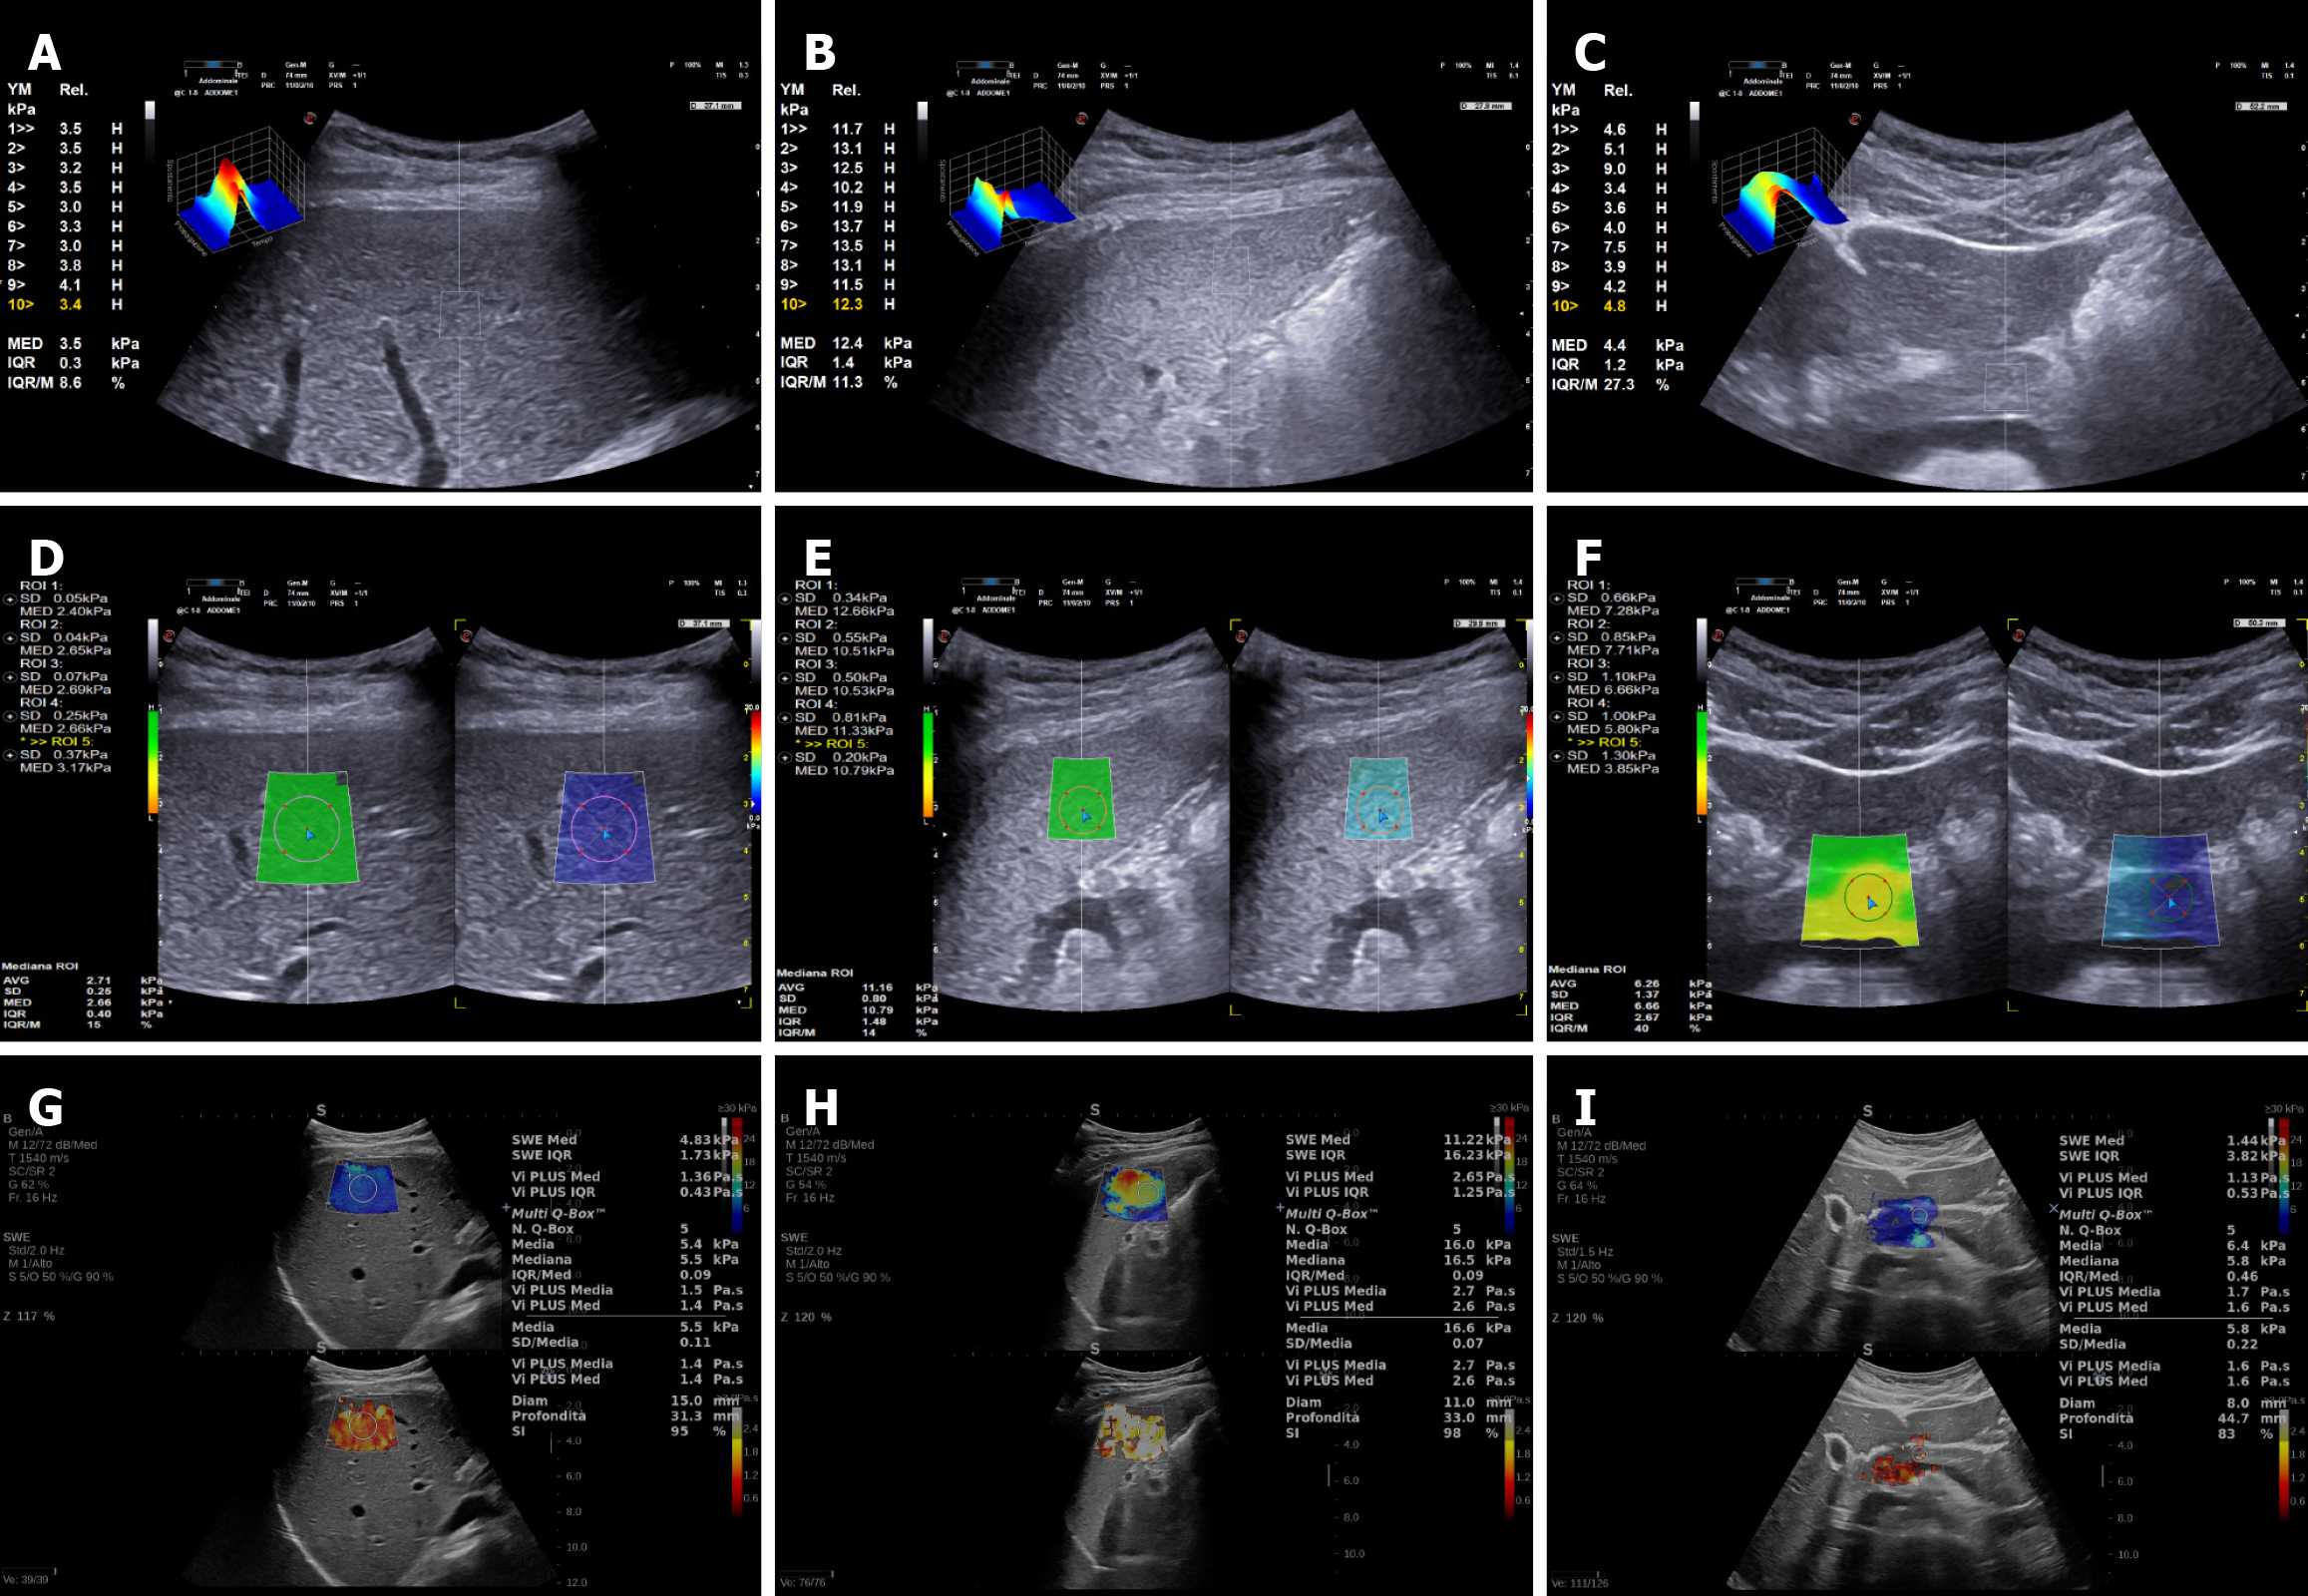

Figure 2 2-dimensional-shear wave elastography of pancreas: Inhomogeneous filling of the colorimetric map suggests an unreliable measurement.